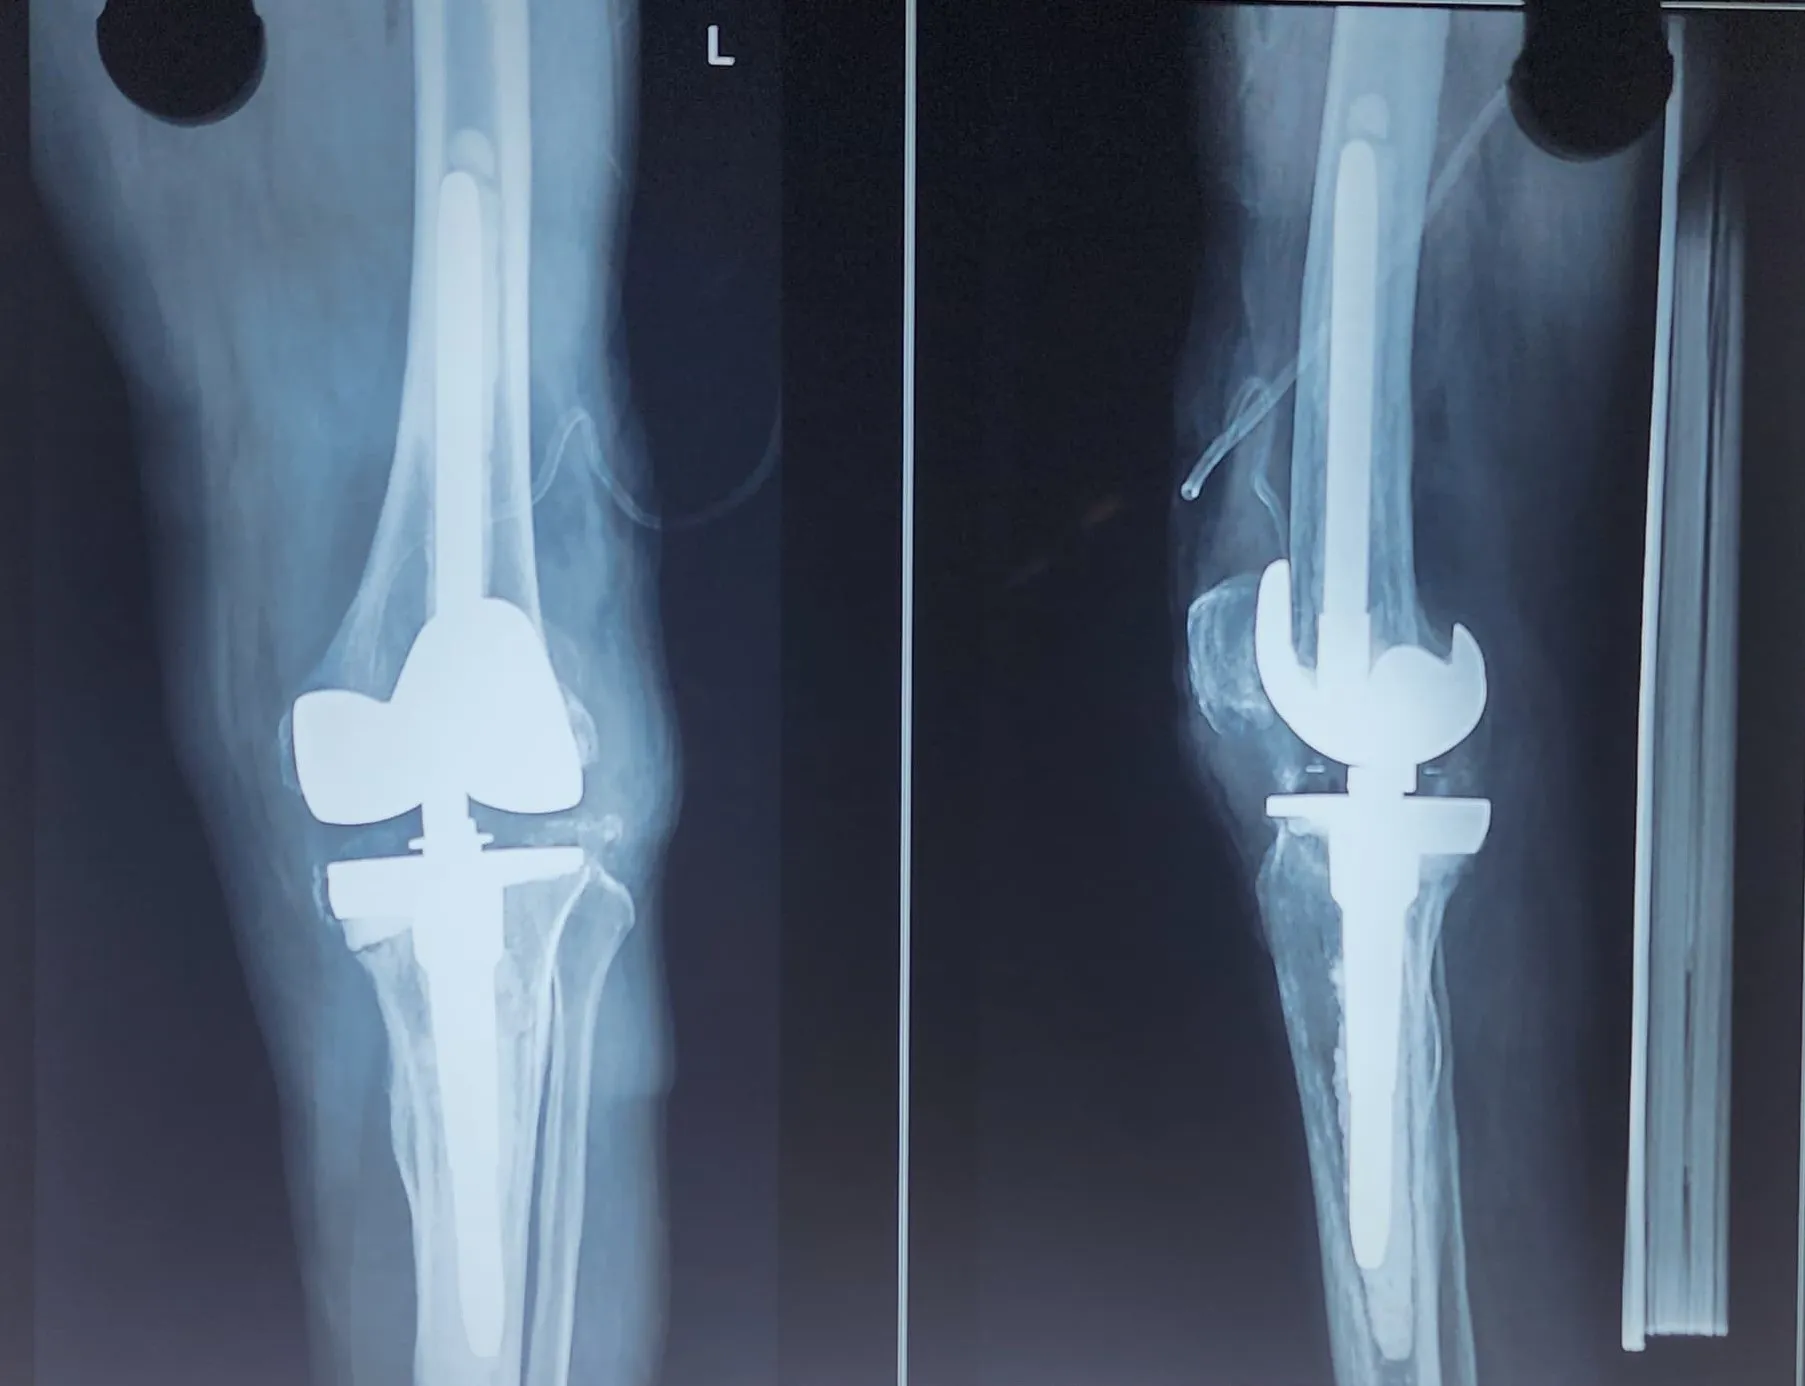

Quality and affordable healthcare has long been the essence in the field of medical sciences & treatment. Every patient expects an early diagnosis and a planned approach to treatment procedures with affordability and access to quality healthcare. Knee replacement, Hip replacement, Fracture treatment are being done by Dr.P.Sankaralingam at very affordable costs without compromising on quality.

Dr.P.Sankaralingam M.S(ortho)., DNB (ortho).,MNAMS is an experienced senior consultant Orthopaedic surgeon who does about 350 joint replacement surgeries per year in addition to treatment of Trauma cases.

• Hip & Knee Replacement and Revision Surgeries

Accomplishment